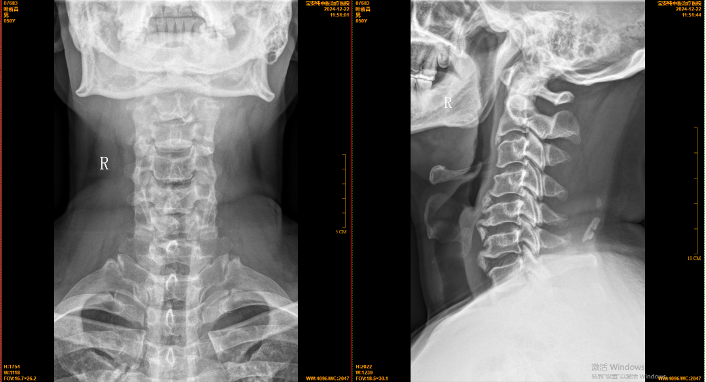

【影像】20250117颈椎X线片报寰齿间距略失对称,颈椎退行性变,C4椎体稍后移。阅片见颈椎上段平直,C4-5失稳,C2-3、C5-6前缘增生,项韧带钙化,右侧寰枢外侧关节对合不全,枢椎棘突略偏左。

【讨论】患者颈及枕部疼痛,颈椎左旋受限;查体C1左侧横突、C2右侧横突压痛(+),右侧头后大直肌紧张、压痛(+);X线片报寰齿间距略失对称,

阅片见右侧寰枢外侧关节对合不全,枢椎棘突略偏左;诊断为寰枢关节半脱位。时有头晕、头痛,考虑与本病相关。